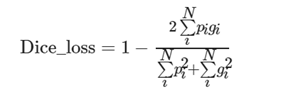

在脑肿瘤检测网络最后的输出层,输出与输入脑肿瘤数据维度相同的脑肿瘤分类概率图,表示每一个体素点是否为脑肿瘤的概率.脑肿瘤检测网络是通过损失函数来计算输出值和标签值之间的误差值,根据误差值来进行网络的反向参数修正,以获得脑肿瘤检测网络最佳的权值和偏置值.在自然图像的目标检测和目标分割任务中,常用的损失函数为Dice_loss,其计算公式为:

在三维MRI脑肿瘤影像中,由于医学影像具有特殊性,与自然图像相比,在整幅脑肿瘤影像中,脑肿瘤病灶区域占比较小,非病灶区域的占比更大.若采用传统的Dice相关性系数作为损失函数,在网络训练过程中,导致网络趋向于对非脑肿瘤病灶区域的特征学习,无法有效提取脑肿瘤病灶区域的特征,从而造成误检和漏检的情况.因此为了提高网络对脑肿瘤区域的学习能力,对传统的Dice_loss损失函数进行了改进,改进后的损失函数计算公式为:

从式(9)可知,由于gi部分对应的是脑肿瘤病灶区域,采用对gi部分进行权值加权,将预测结果和金标准在损失函数中的占比分为1:3.通过加权的方法,损失函数对金标准分配的损失系数更大,能够加强网络对脑肿瘤病灶区域的特征学习,弱化网络对非肿瘤区域的损失值分配,减小了脑部MRI背景影像对病灶区域特征学习的干扰,从而提高网络的检测准确率.